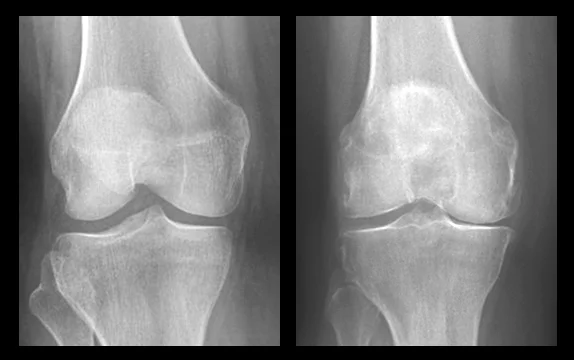

(ภาพซ้าย) เอ็กซเรย์ของข้อเข่าปกติ

(ภาพขวา) เอ็กซเรย์ของข้อเข่าที่เสื่อมสภาพ

ยิ่งอายุมาก ยิ่งใช้งานเข่ามานาน ข้อเข่าก็ยิ่งเสื่อมสภาพมากขึ้นตามลำดับ เข่าที่เสื่อมสภาพมักจะพบว่ามี การสึกหรอ บิดเบี้ยวผิดรูปของข้อเข่า กระดูกอ่อนบริเวณหน้าสัมผัสของข้อเข่าและกระดูกเข่าบางลง กล้ามเนื้อขาและรอบข้อเข่าเล็กลง มีความแข็งแรงลดน้อยลง ช่องว่างในเข่าแคบลง และมีน้ำหล่อเลี้ยงในเข่าน้อยลง ซึ่งส่งผลต่อเนื่องให้เส้นเอ็นภายในและรอบๆเข่าขาดการหล่อเลี้ยงจนสูญเสียความยืดหยุ่น

ภาพข้อเข่าปกติ (ด้านซ้ายมือ) เปรียบเทียบกับข้อเข่าที่เสื่อมสภาพ (ด้านขวามือ)